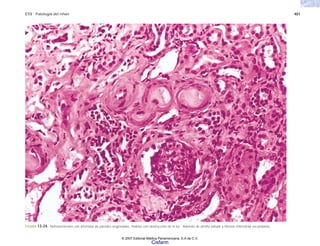

FIGURA 2-7. Mieloma múltiple. a) Histología de la neoplasia. b) Citología de un

frotis del tumor, que permite apreciar la morfología de las células plasmáticas

neoplásicas. (Cortesía del Dr. Joaquín Carrillo.)